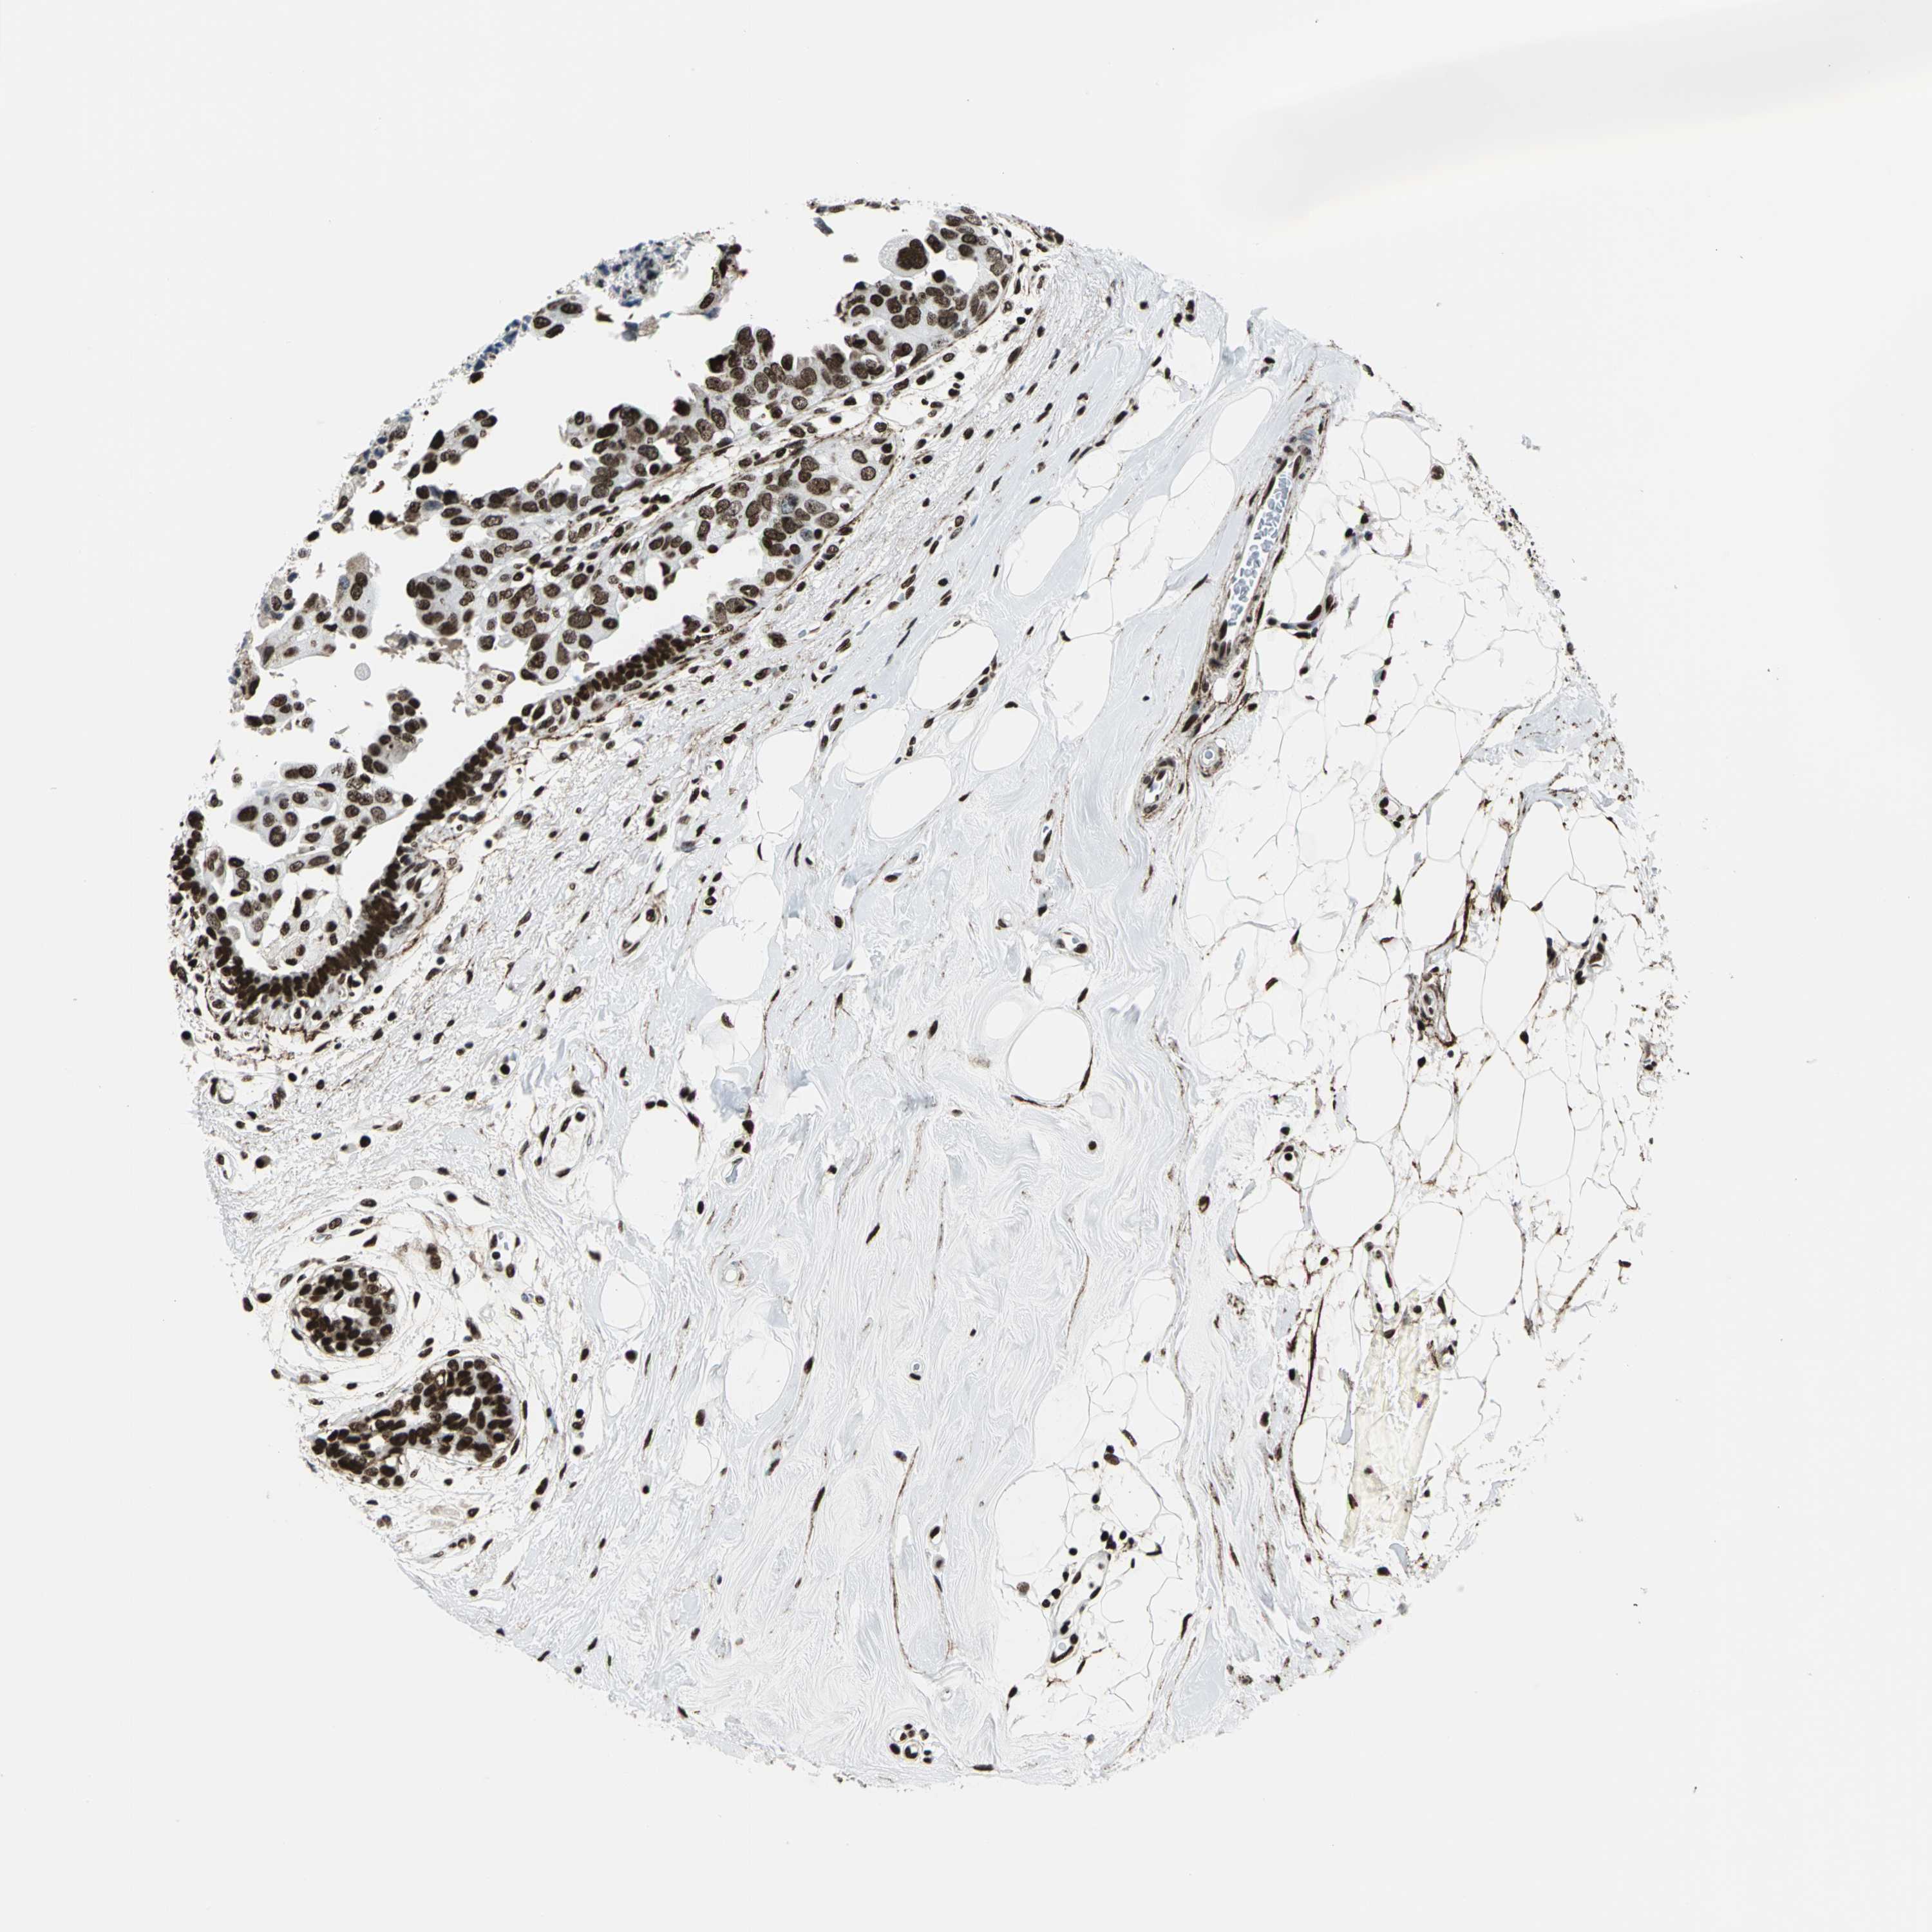

APEX1

CANCER BREAST CANCER Show tissue menu

BRCA TCGA BRCA VALIDATION PROTEIN EXPRESSION

ANTIBODIES

AND

VALIDATION